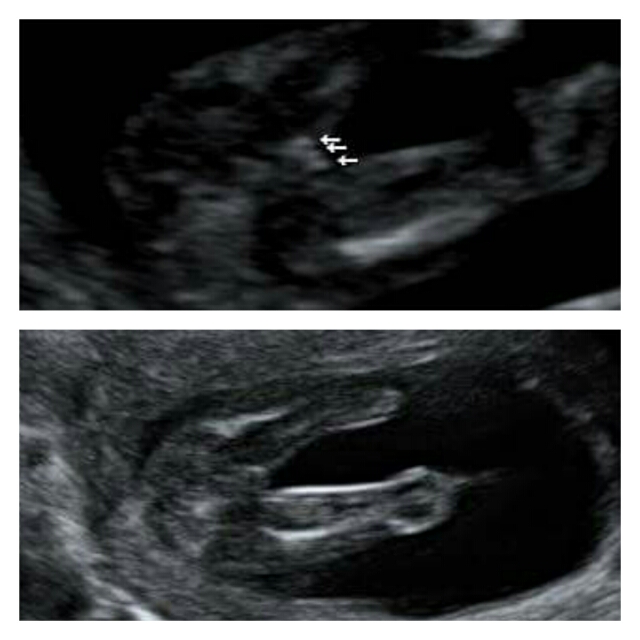

We had a private scan at 16 weeks and were told GIRL! I was so excited and over the moon, I'd already convinced myself it was another boy to prepare myself and it all changed!! I've had doubts since that day and so tried not to become connected to a daugher, however nature has taken its course and I've bonded with my girl and named her Ivy-Rose! My 20 week scan is on Tuesday 1st Dec and I'm petrified, i'm worrying this doubt is a sign and my dream girl is going to be snatched away. I just want baby to be healthy of course but can't get this out of my head. So come on, do you think there is a chance that this baby could end up being blue, that ball shape on bottom pic is whats throwing it for me .....

Attachment 28721